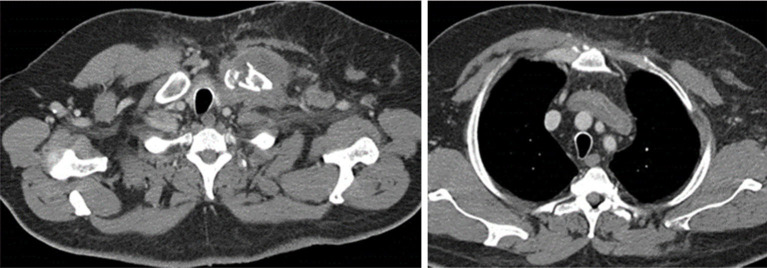

Case description: A 70-year-old patient with type-A thymoma underwent a via sternotomy thymectomy with an end-to-end caval anastomosis and an end-to-side anastomosis with the left brachiocephalic trunk by prosthesis. A 52-year-old patient with malignant peripheral nerve sheath tumor of left sternocleidomastoid muscle underwent surgical excision and chest wall reconstruction by Teflon prosthesis and pedicled flap from the rectus abdominis. A 41-year-old woman diagnosed with monophasic synovial sarcoma of the anterior mediastinum. After chemotherapy without benefit, she underwent debulking surgery with excision of this huge mass and right phrenic nerve reconstruction by neural graft from the contralateral phrenic nerve. A 23-year-old woman affected by myasthenia gravis (MG) with a type-B3 thymoma diagnosis. After chemotherapy without benefit, she underwent a thymectomy and left pneumectomy with reconstruction of the superior vena cava (SVC).